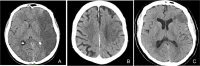

The objective of this manuscript is to describe the challenges of Cardio-Cerebral Infarction (CCI) treatment and to highlight the variable approaches in management. CCI is a rare clinical presentation of simultaneous acute ischemic stroke (AIS) and acute myocardial infarction (AMI) and poses a therapeutic challenge for practitioners. Each disease requires timely intervention to prevent irreversible damage; however, optimal management remains unclear. We describe three cases of CCI. All three patients presented with symptomatic left MCA (M1) occlusion, with ST elevation myocardial infarction (STEMI) and left ventricular apical thrombus. Fibrinolysis and mechanical thrombectomy (MT) were discussed in all cases, but only one patient received alteplase (0.9 mg/kg) and none underwent MT. Percutaneous intervention (PCI) was done in only one case. The two patients that did not receive thrombolysis were treated with modified therapeutic heparin (no bolus), and all received antiplatelet therapy. Ultimately, all three patients passed away. CCI poses a clinical challenge for physicians including (1) optimal strategies to enable swift mechanical reperfusion to both the brain and myocardium; (2) difference in dosage of thrombolytics for AIS versus AMI; (3) risk of symptomatic intracerebral hemorrhage following administration of anticoagulation and/or antiplatelet therapy; and (4) caution with use of thrombolytics in the setting of acute STEMI due to the risk of myocardial rupture. In the absence of high quality evidence and clinical guidelines, treatment of CCI is highly individualized.